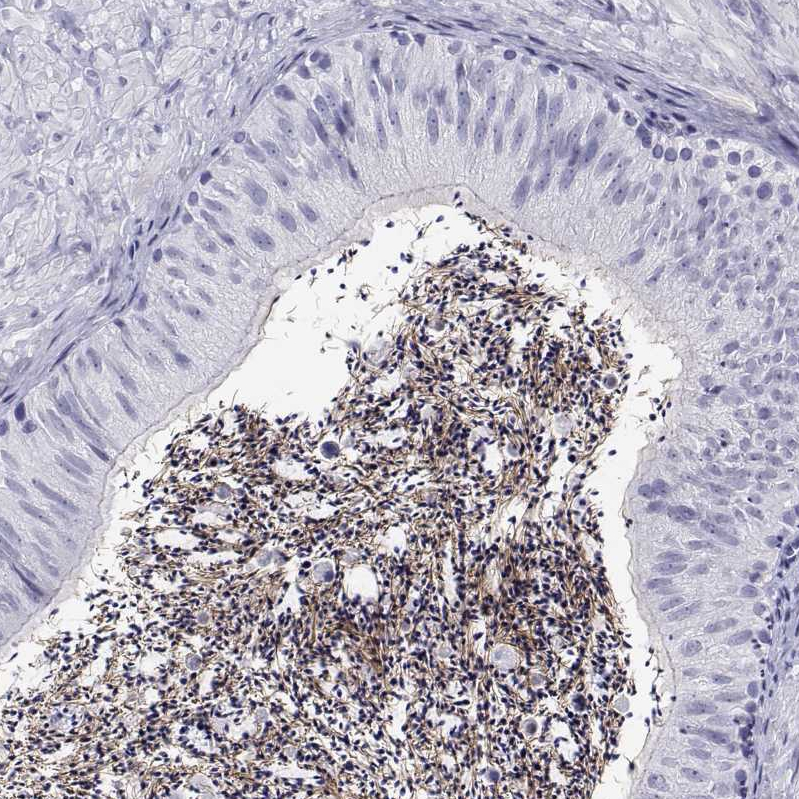

Immunohistochemistry analysis in human testis and liver tissues using HPA052219 antibody. Corresponding QRICH2 RNA-seq data are presented for the same tissues.